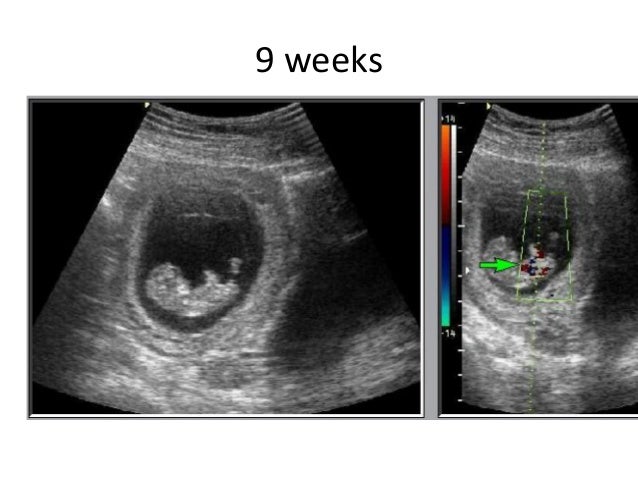

normal first trimester ultrasound sorted by